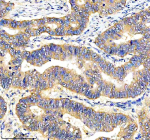

Immunohistochemical staining of DEPDC6/DEPTOR using anti-DEPTOR antibody. DEPDC6/DEPTOR was detected in a paraffin-embedded section of human lung cancer tissue. Heat mediated antigen retrieval was performed in EDTA buffer (pH 8.0, epitope retrieval solution). The tissue section was blocked with 10% goat serum. The tissue section was then incubated with 2 ug/ml rabbit anti-DEPTOR antibody overnight at 4oC. Peroxidase Conjugated Goat Anti-rabbit IgG was used as secondary antibody and incubated for 30 minutes at 37oC. The tissue section was developed using an HRP secondary and DAB substrate.